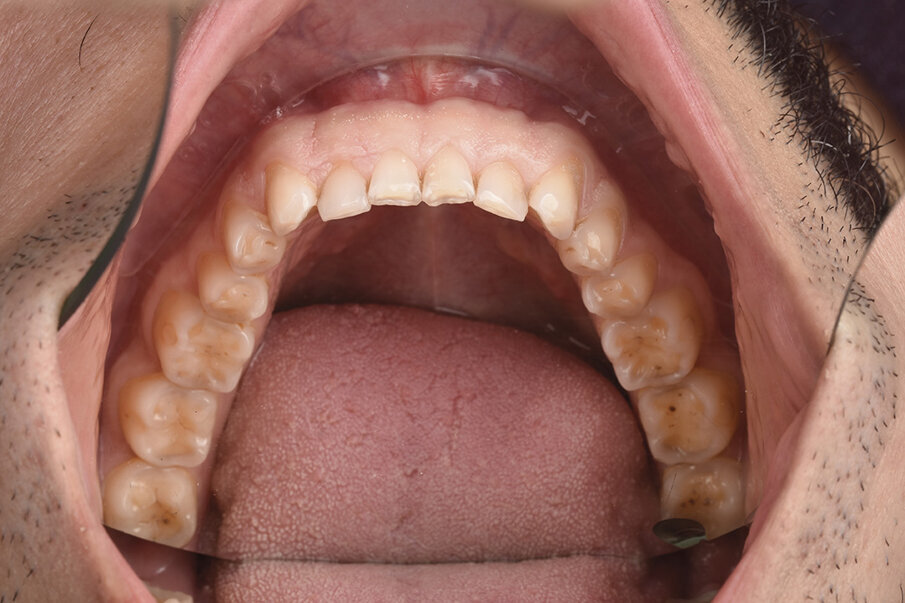

4. Ekstraoralni i intraoralni fotoprotokol (Sl. 1- 4).

5. Skeniranje zuba

-Intra oralni sken inicijalne situacije

-Intra oralni sken na zadatu, željenu visinu pomoću jig-a (Sl. 5)